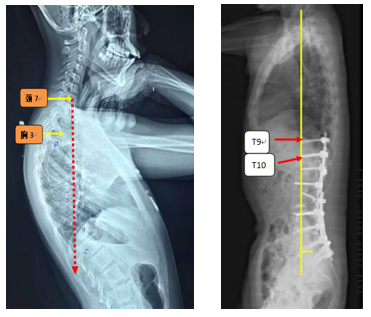

Ø 颈7铅垂线距离UIV太远

图19 颈7铅垂线距离UIV太远

Ø 上固定椎在上终椎的尾端

图20 Lenke 1型脊柱侧弯上固定椎(UIV)选择在上端椎(UEV)的尾端是导致PJK的危险因素